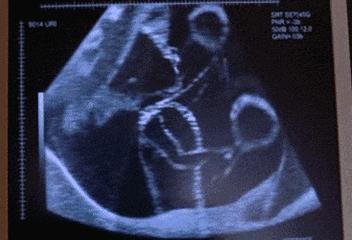

一次孕早期(11-13+6周)严重致死致残性结构畸形超声筛查(含NT);

一次孕中期(18-24周)严重致死致残性结构畸形超声筛查(II级产前超声检查)。